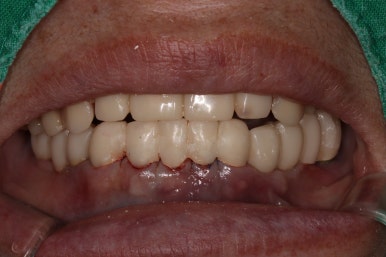

그렇게 완성된 최종 보철물 형태입니다.

임시치아와 다르게 지르코니아 크라운으로 제작되어 훨씬 단단하고 매끈하고 이상적인 형태를 가진걸 보실 수 있으실거에요.

위 아래 앞니 모두 적절한 길이로 회복이 되었고, 어금니도 이상적인 형태를 보여주고 있습니다.

좌우로 옆에서 봤을 때도 충분히 기능이 잘 되게끔 잘 물리는 어금니를 보실 수 있을거에요.

식사 시 음식이 덜 끼도록 치아와 치아사이를 최대한 닫아놓은 모양입니다.

위아래 모두 아주 이상적인 형태로 제작된 치아모양의 지르코니아 크라운을 보실 수 있을거에요.

이 정도면 전체 구강 재건 (full arch rehabilitation)이라고 불러야 합니다.

상당히 난이도가 있는 케이스이며, 완성후에 자연스럽게 사용하시게 되려면 정말 경험 많은 치과의사가 필요합니다. 이를 위해 보철과 전문의와의 협진은 상당히 좋은 시너지를 내죠.